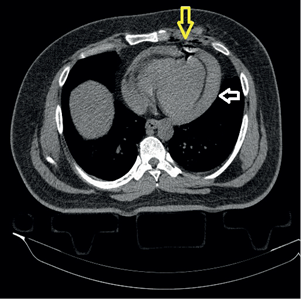

On computed tomography (CT) scan view was possible to see the bullet on the right lobe of the liver. A CT of the chest and abdomen revealed hemopericardium, a small pneumopericardium (Figure 2), and the bullet on Couinaud’s segment IV of the liver (Figure 3).

The patient remained hemodynamically stable. Underwent subxiphoid pericardial window positive for blood. Then a left thoracotomy was performed, the pericardial sac was open and several clots were evacuated from it, the heart was cleaned with saline solution, no cardiac injury was found. No injury to the heart was seen, but there was an important pericardial injury on the diaphragmatic surface